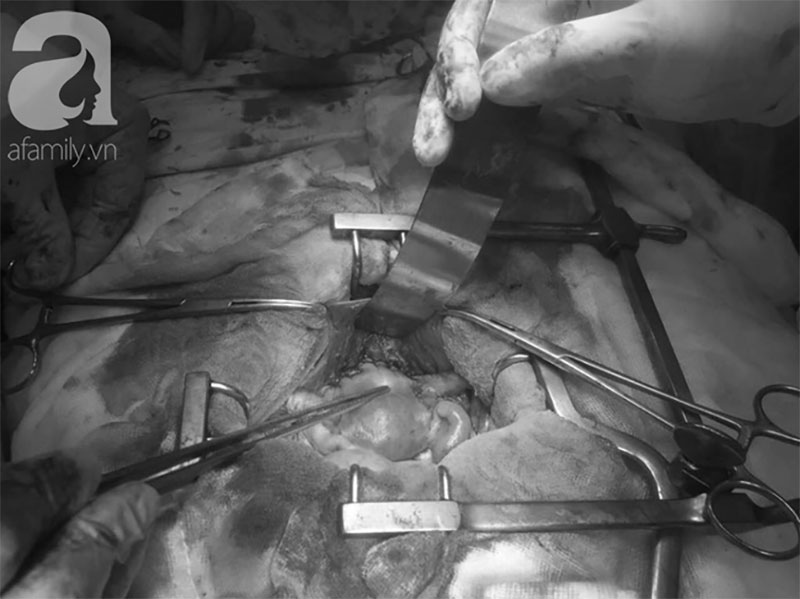

Ekip điều trị tiến hành mổ khẩn cho bệnh nhi, tuy nhiên cuộc phẫu thuật thất bại vì bướu đã xâm lấn toàn bộ tử cung, bàng quang, vách hạch chậu và hạch cạnh động mạch chủ bụng.